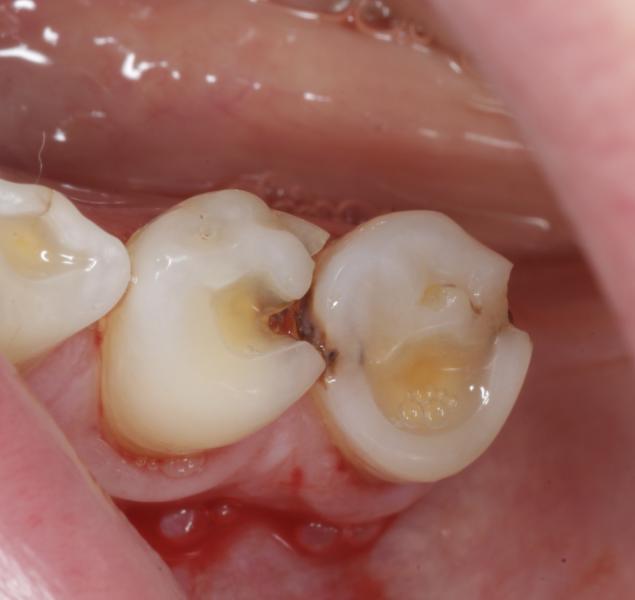

Возрастная пациентка

Лечение кариеса/ пульпита